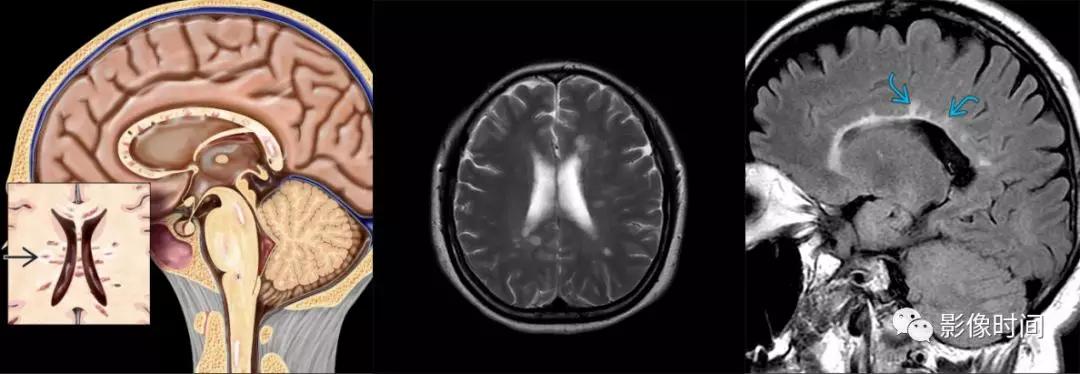

多发性硬化(Multiple sclerosis,MS)亦是一种严重的中枢神经系统自身免疫脱髓鞘病变,免疫球蛋白分泌 B 细胞和浆细胞的克隆性扩增,可使 CSF 中出现寡克隆带特征。

MRI:

脊髓:颈髓较常受累,病灶 T2WI 呈高信号,T1WI 呈稍低信号,轴位常分布于前索、侧索或者后索,长轴 ≤ 2 个连续阶段椎体,急性期呈斑片状、结节状或环形强化。

病灶位于侧索、长度小于3个椎体节段

大脑:病灶常呈卵圆形,病灶长轴与侧脑室前后径垂直,沿深髓静脉分布,「Dawson 手指征」

病灶长轴垂直于侧脑室分布